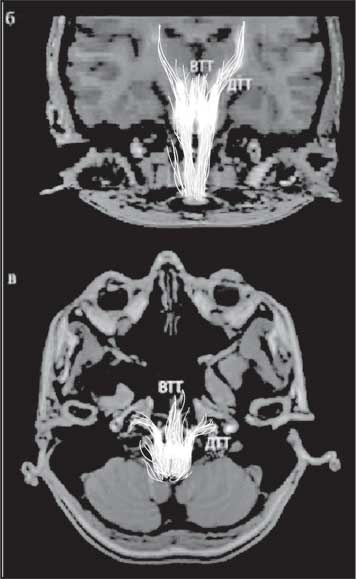

Рис. 12. Схематичный вариант визуализации волокон ретикулярной формации (воспроизведенный художником)

Важно отметить, что в последние годы сканирующие методы исследования продвинулись далеко вперед. В 2018 году в НИИ нейрохирургии имени академика Н. Н. Бурденко впервые на группе здоровых людей была разработана методика визуализации очень тонких пересекающихся волокон сетчатой структуры ретикулярной формации. Эта методика дала врачам мощный инструмент для оценки степени поражения головного мозга. Такие данные позволяют отразить исход восстановления сознания, а также интеллектуальной и эмоциональной сферы человека. Это приближает нас к более персонифицированному уровню диагностики.